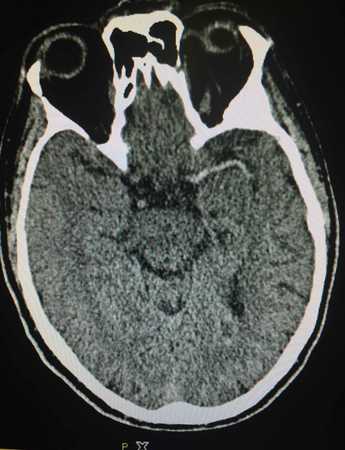

患者男性,23 岁,临床表现神清合作,中度贫血貌,对答切题,言语表达正常,右额颞头面部及胸背部可见大片咖啡样色素斑块沉积,右额颞部巨大头皮包块,约16 cm×12 cm×26 cm 大小,右侧眼睑水肿,结膜充血,眼球脱出眼眶、红肿,已失明,左侧视力尚可,瞳孔形圆,对光反射存在(图1)。面部感觉可,露齿、鼓腮正常,口角无歪斜,双侧听力粗测正常,余颅神经正常,躯体浅深感觉正常,四肢肌力、肌张力正常,颈阻阴性,双侧肢体共济运动正常,双侧膝反射正常,双下肢病理征未引出。 血常规:WBC 8.0×109/L,RBC 3.0×109/L,Hgb 92 g/L,PLT 276×109/L。肝肾功能未见明显异常。入院头颅增强CT及CTA(图2):右侧眼眶增大,右侧眼眶球后可见一不规则肿块影,边界尚清,CT值约16 HU,密度尚均匀,范围约3.8 cm×10 cm×3.3 cm,增强后未见明显强化,右侧眼眶眶壁受压并见骨质变薄,右侧眼球受压、变形并向右前移位,邻近眼肌及视神经受压前移,右侧眶尖明显增大,病灶经眶尖向右侧蝶窦、右侧海绵窦及鞍区生长,右侧额部皮下可见一巨大不规则肿大影,平扫呈高、低混杂密度影,增强后明显不均匀强化,范围约16 cm×12 cm×26 cm,邻近额骨、颞骨、颧骨骨质明显变薄并稍毛糙,骨质未见确切中断,病灶与周围肌肉分界欠清;左侧额骨局部呈膨胀性骨质破坏,其内密度不均匀,可见多发结节高密度影,骨皮质未见中断,周围未见确切肿块形成。心电图:大致正常心电图。腹部B 超:未见明显异常。 患者病情进展快,针吸细胞学检查未能明确病理,病变性质尚不明确,结合病史、头颅CT 及CTA 检查,临床考虑神经纤维瘤伴瘤卒中可能性大。患者手术指征明确,无绝对手术禁忌,与家属充分沟通后于2014年11月5日行全麻下右额颞部颅眶沟通巨大神经纤维瘤切除术,手术较顺利(图3)。术中失血多,出血约1600 ml,输血800 ml,术后予抗炎、止血、营养支持等治疗,因患者贫血较明显,输红细胞悬液400 ml 支持治疗。